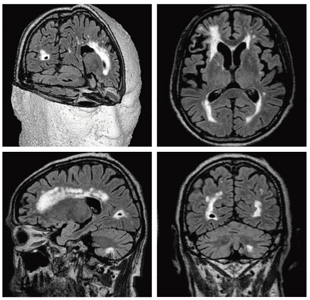

1.Cube

Cubeは,アイソトロピックなボリュームデータでT2強調やプロトン密度強調,FLAIRを得ることができる撮像法である。アイソトロピックな分解能を有するため,1度撮像を行えば,後から任意の断面にリフォーメーションを行うことで高品位な画像を提供することが可能である(図4)。 従来の3D FSE法では,エコートレインを長くすると,T2減衰によるブラーリングが問題となるほか,実効TEが延長するため,主にMRCPなどのheavy T2強調の撮像に用途が限定されていた。Cubeでは,リフォーカスパルスのフリップアングルを変化させることで,非常に長いエコートレインでのデータ取得を可能とし,そして,通常のFSE法とコントラストが大きく変わることのないようリフォーカスパルスの最適化を行っているため,コントラストの良好な高分解能画像を取得することができる。

今回新たに加わったパラレルイメージング手法である“ARC”を併用することで,元来“ASSET”が苦手としていたFOVを絞った状態でのパラレルイメージングによる撮像の高速化も可能となり,より高分解能な画像が,短時間で容易に取得できるようになった。なお,通常の3D FSE法より小さなリフォーカスパルスを連続的に用いるため,SARの大幅な低減も実現している。

図4 CubeによるFLAIR撮像(1.5T)

アイソトロピックな分解能で撮像しているため,

リフォーマットしても良好な画像が得られる。

(画像ご提供:東京大学医学部附属病院様)